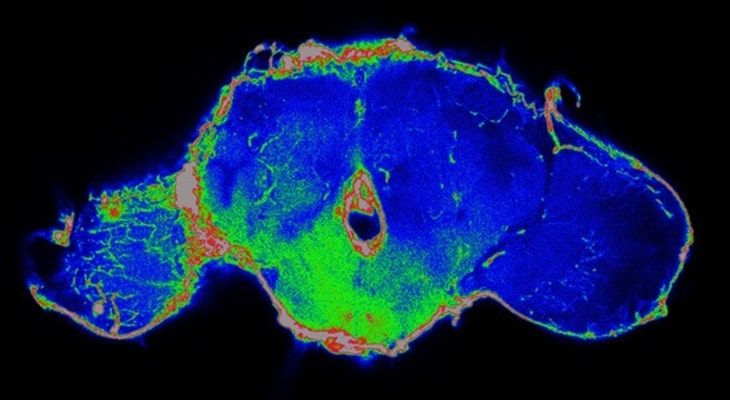

The fruit fly research that is being conducted at the University of California-Berkley could help scientists figure out the reason behind the death caused by the cancer tumor cells apart from the critical organ failure. The fruit fly research suggests that the lifespan of cancer patients could be improved if we deal with the effect that tumors have, rather than the conventional removal of the tumor cells. Researchers monitored the fruitflies that had cancer cells and found out that they release a chemical that breaks the barrier between the bloodstream and the brain which can lead to many diseases like infections, trauma, and obesity.

David Builder (professor of molecular and cell biology at UC Berkley), and Jung Kim( a fellow at Bilder’s lab) collaborated with the professors David Raulet and Kaoru Saijo and noticed that tumors in mice release the same chemical called interleukin-6 which is responsible for interfering with the blood-brain barrier.“The IL-6 cytokine is known to cause inflammation. What’s new here is that this tumor-induced inflammation is actually causing the blood-brain barrier to open. If we interfere with that opening process but leave the tumor alone, then the host can live significantly longer and healthier with the same tumor burden,” Bilder enlightens. Therefore, the fruit fly research suggests that dealing with the harmful chemical that cancer cells produce, might actually help increase the life expectancy of the patients.